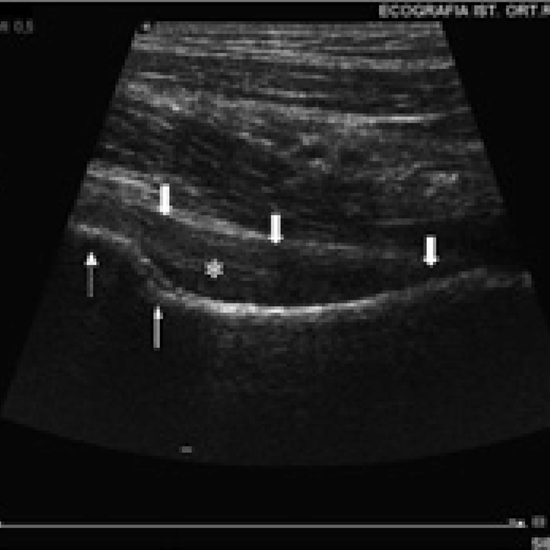

Hip ultrasound uses sound waves to create images of the hip's muscles, tendons, ligaments, joints, bone, and soft tissues. It is used to aid in the diagnosis of abnormalities and may be used in infants to screen for hip developmental dysplasia. Ultrasound is non-invasive, safe, and does not emit ionising radiation.

The doctor prescribes this test to aid in the diagnosis of unexplained discomfort, oedema, or infection. It is also helpful for detecting developmental dysplasia, the most prevalent musculoskeletal disorder in neonates that causes the hip to become dysplastic and dislocate.